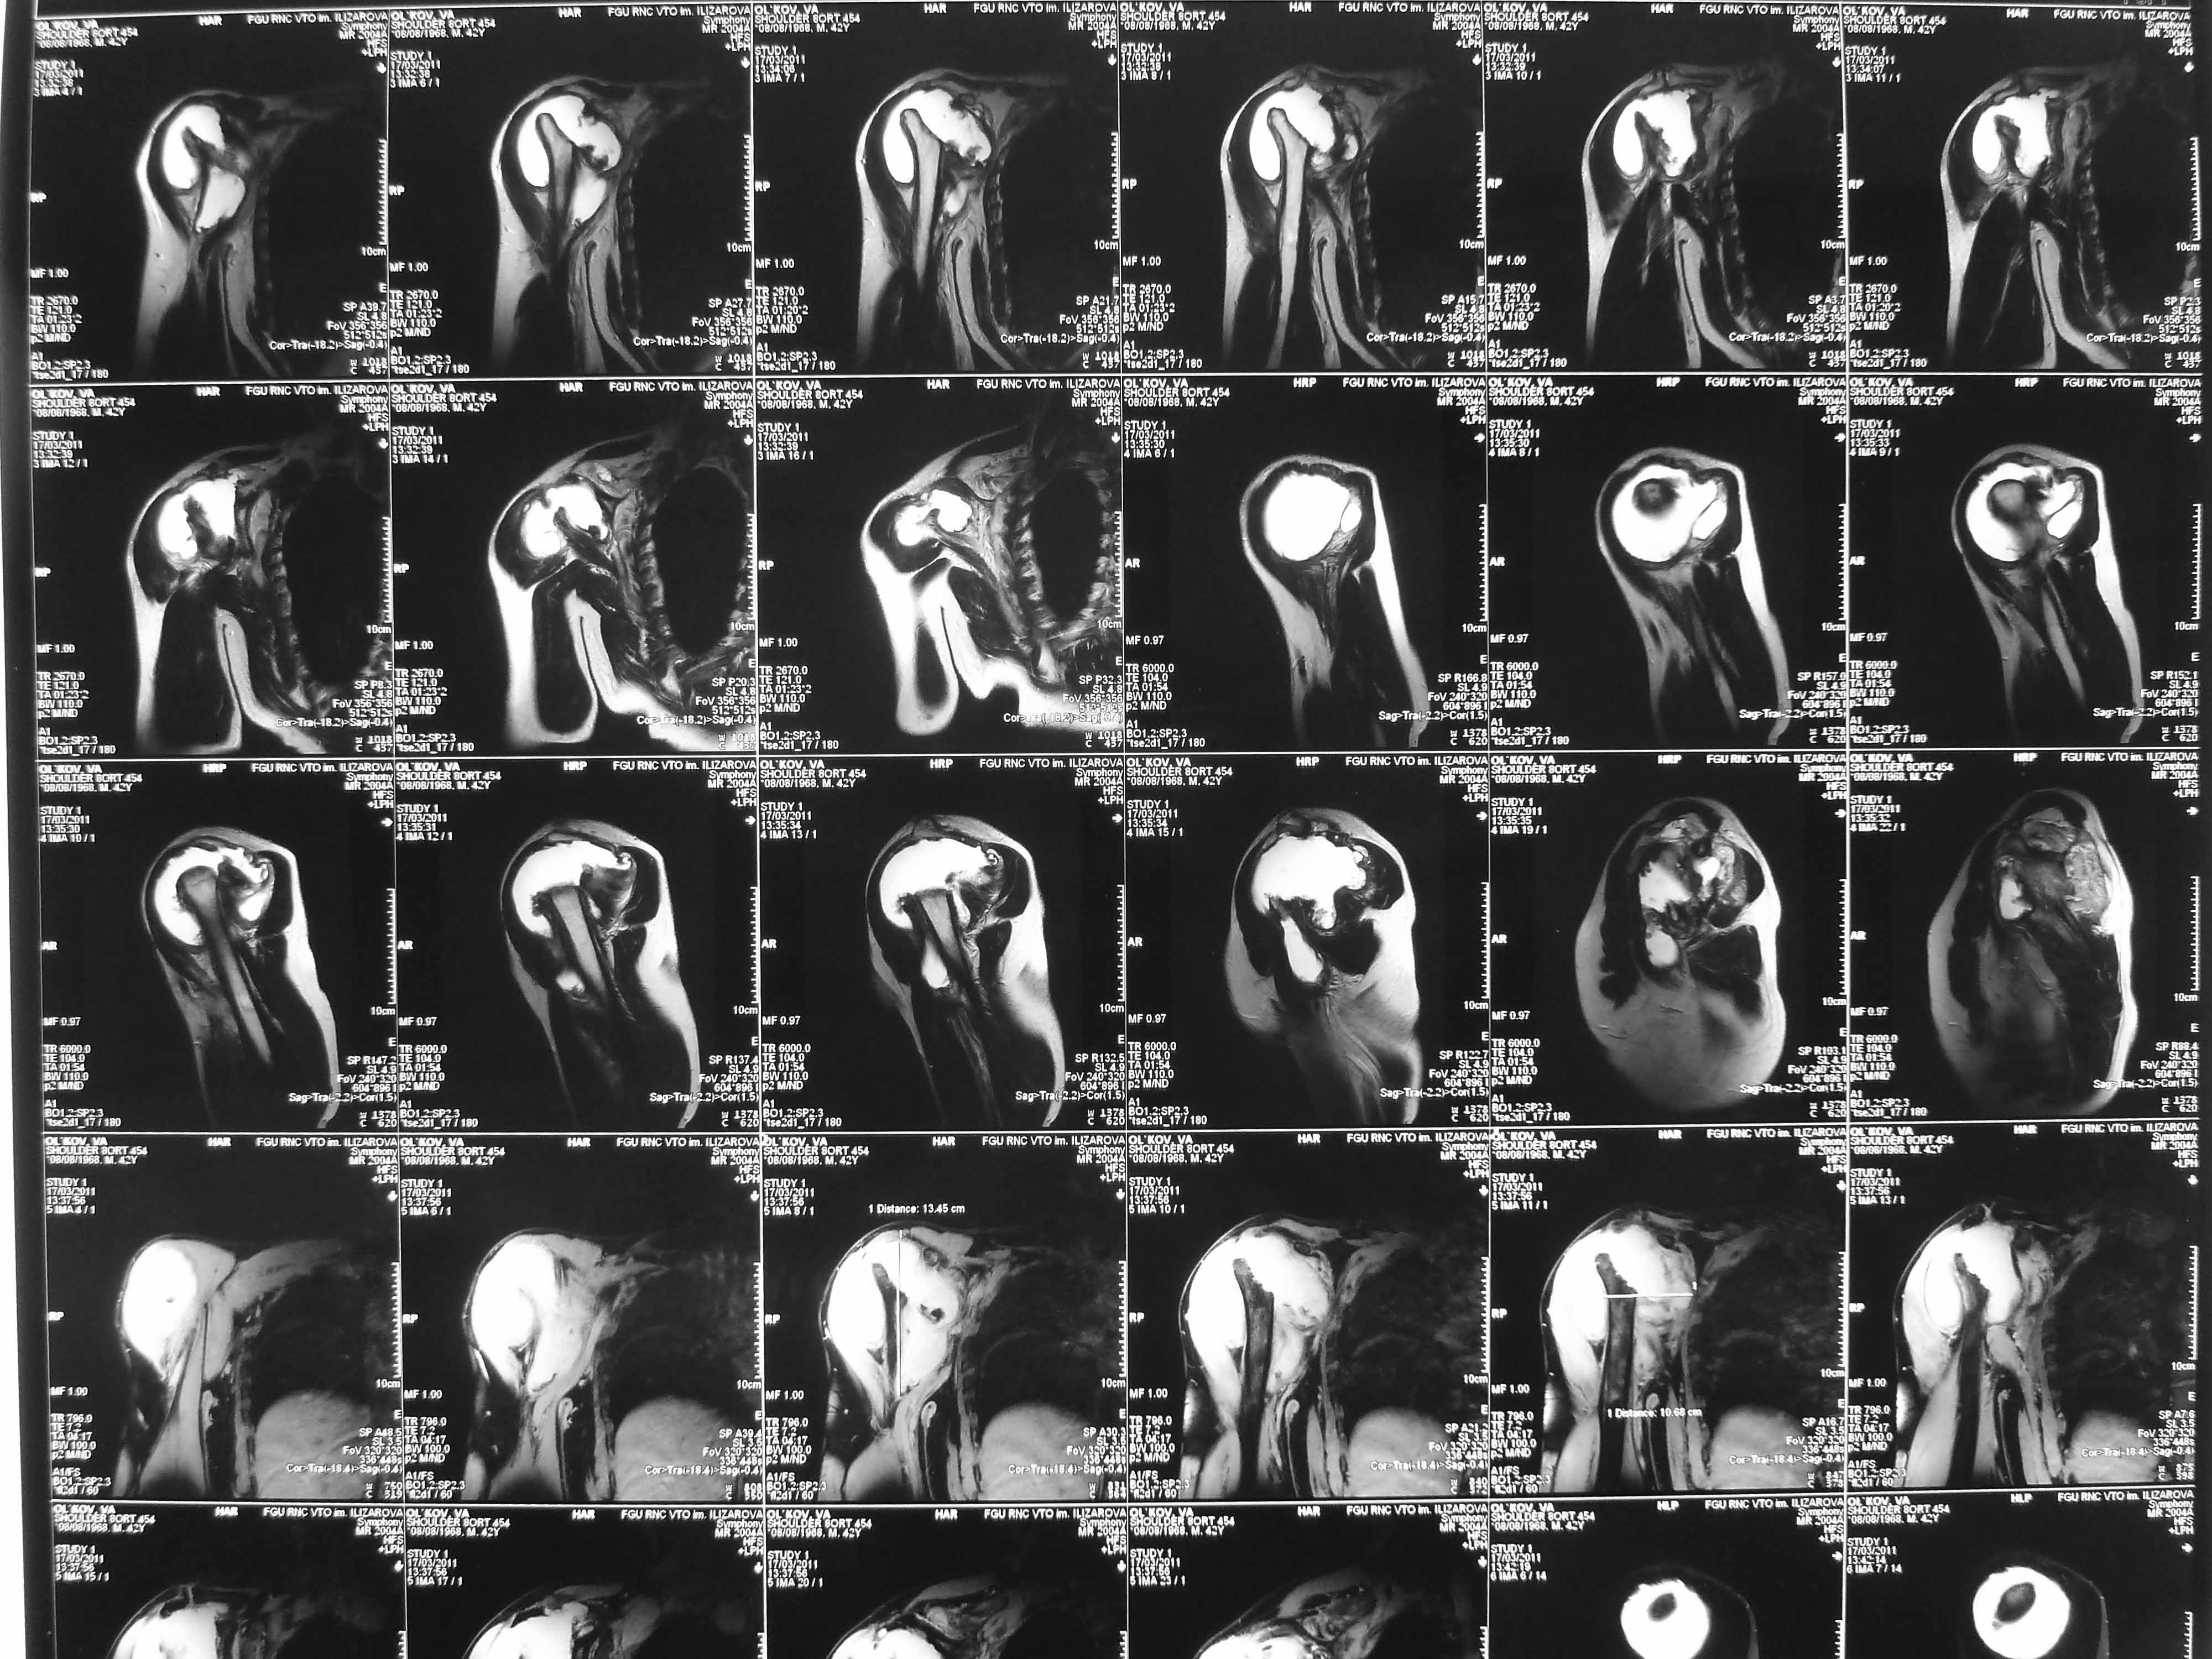

Несколько лет назад информация по поводу беcпричинного массивного остеолиза в плечевом сустава была выставлена на ОртоФоруме. Возможно, я ошибаюсь, но описанная клиника больше подходит к редкой болезни Gorham’s disease. Заболевание имеет множество синонимов, но главным симптомом заболевания является характерное разрушение и резорбция кости. В зависимости от клинических проявлении лечение различается, от лучевой терапии до анти остеокластических (bisphosphonate), а также alpha-2b-interferon.

Поэтому будьте внимательны, прежде чем предлагать методы лечения, сперва необходимо провести дифференциальную диагностику со множественными сходными состояниями или сделать хотя бы обычные снимки. Компьютерное Томографическое Исследование также поможет найти причину исчезновение кости и замены сосудистой структурой.

Не усмотрел в анамнезе "ноябре 2009 - травма с потерей сознания. В феврале 2010 г - первый рентген правого плечевого сутава - перелом анатомитеской шейки".

Все таки "The first is characterized by vascular proliferation in connective tissue, which is consistent with hemangiomatosis and the second by replacement of the resorbed bone by fibrous tissue" Massive Osteolysis of the Hip: Gorham’s Disease by Panagiotis Stavlas, MD; Vassiliki Katsiva, MD; Yiannis Kouvaras, MD

Поэтому желательно выставить все рентгенологические и данные МРТ для сравнения со снимками из статьи.